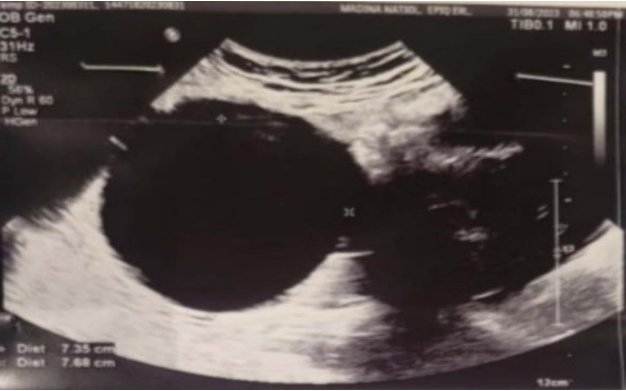

The left adnexa show a well-defined cystic lesion of about 6.7x8.6 cm, likely a left simple ovarian cyst, the cyst is surrounded by localized minimal to mild fluid collection around it, with tenderness on probing, by Doppler study, and it shows vascular flow however the possibility of ovarian torsion couldn't be excluded. Figure (2).

Fig 1, Fig 2

Figure 2